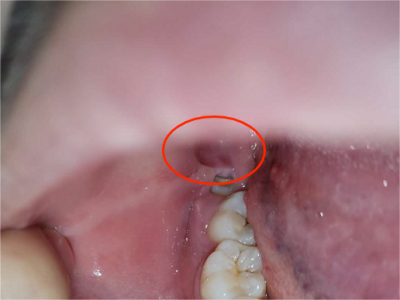

智齿冠周炎右下方的牙龈最内侧红肿图

智齿冠周炎患者右下方的牙龈最内侧有红肿,红肿处有一小创口,可见其内的牙齿,牙齿未完整露出,小创口边缘微微发白,患者自觉有明显疼痛。